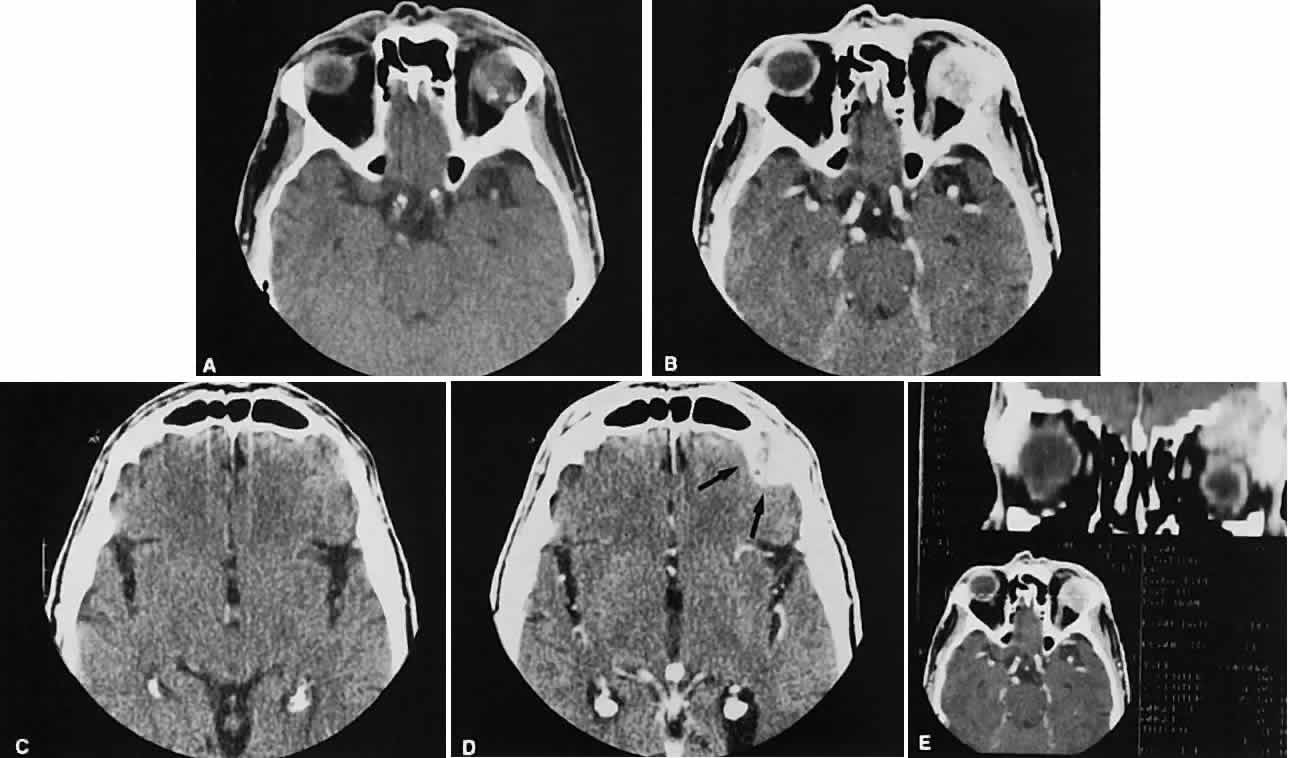

| CT scanning is a valuable tool in the management of orbital trauma. Appropriate

windows allow optimal visualization of bone (fractures) and soft

tissue (foreign bodies, emphysema, hematomas, entrapment). There is

no “standard set” of films to obtain for trauma, and communication

with a radiologist beforehand is essential for the best study. The

recent introduction of spiral (helical) CT has facilitated the

evaluation of trauma patients.72–74 Scanning times with this new scanning technique have markedly decreased, an

important consideration with a combative or uncooperative patient. There

also is less radiation exposure. Direct coronal views (3-mm) by themselves, without contrast, probably give the most information about the orbit in a trauma evaluation. Subtle nondisplaced fractures can be seen, and soft-tissueentrapment also may be appreciated (Fig. 22).Blowout fractures of the floor and medial wall are straightforward in their radiologic assessment. Rounding of the inferior rectus muscle can be a helpful radiologic clue to the presence of a floor fracture if the fracture itself is not seen on the scan.75 “Blow-in” fractures of the roof need to be scrutinized carefully for frontal sinus fractures and pneumocephalus, which, if untreated, could lead to a cerebral abscess.76,77

The last trauma consideration here is traumatic optic neuropathy associated with an optic canal fracture. Trauma directed at the brow is a common precursor to this type of lesion. Detailed evaluation of the optic canal is not routine, and a high index of suspicion is required on the part of the clinician and the radiologist to adequately evaluate this area radiographically. |